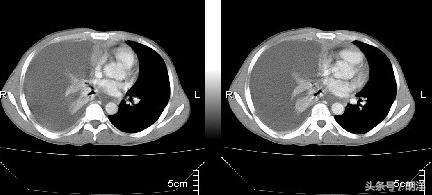

结核性胸膜炎会有很明显的胸痛症状,这个症状可以为隐痛也可以为剧烈的疼痛,并且和呼吸相关,深吸气是疼痛的程度会加大,这是由于胸膜上除了密布血管和淋巴管之外,痛觉神经也非常丰富,有炎症时更加敏感,两层贴在一起的胸膜随着呼吸会发生相对的运动产生摩擦,这时候就会引起剧烈的疼痛感。但这种疼痛感会随着胸腔积液的产生和增多而逐渐减弱和消退,这是由于胸腔积液产生后就会隔开两层胸膜不会产生摩擦而致。除了胸痛之外,结核性胸膜炎还会有结核感染的所有其他症状,比如发热,盗汗,咳嗽,乏力,消瘦,食欲不振等。